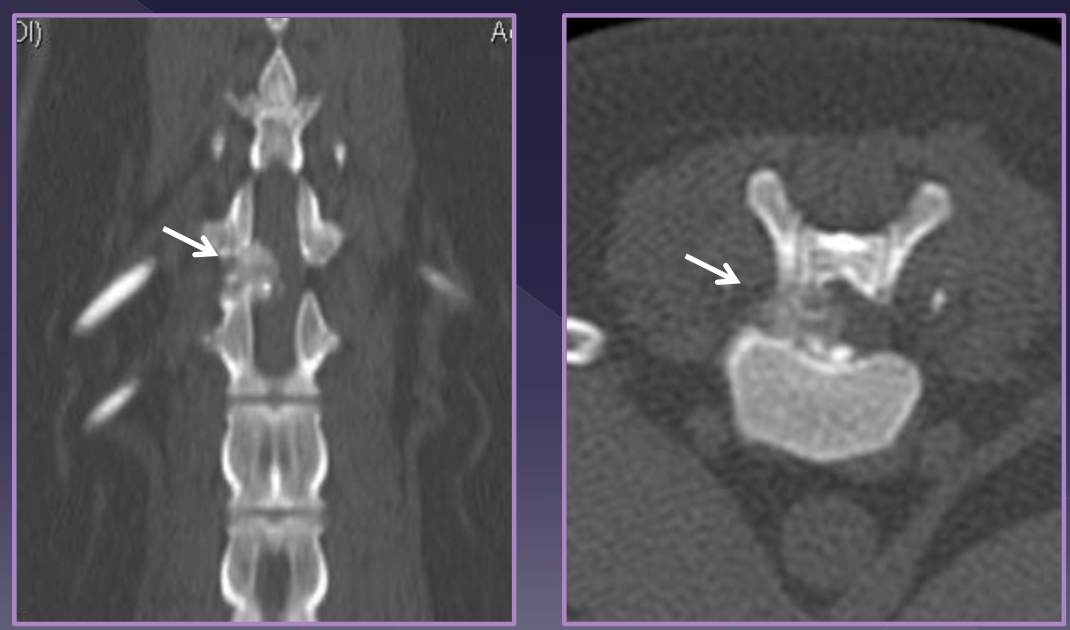

Diagnosis of intervertebral disk herniation

spinal radiographs

35% accurate

rule out differentials

diskospondylitis

neoplasia

trauma

identify

foraminal changes / mineralization

narrowing/wedging of disc space

mineralized disk IN SITU

CT

MRI